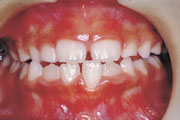

一般矯正の症例

症例3:開咬(オープンバイト)